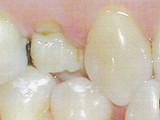

La couronne sur dent vivante

Il est aujourd'hui possible de conserver une dent vivante tout en la protégeant par une couronne, à certaines conditions.

La solution recommandée est de recouvrir la dent par une couronne assurant toute l'étanchéité voulue, protégeant des atteintes thermiques et autres agressions.

Il est possible de répondre aux impératifs fonctionnels en rétablissant l'engrenage parfait avec les autres dents (esthétique, mastication, solidité...).